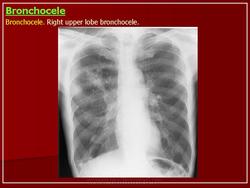

Бронхоцеле

Бронхиальная атрезия

- в результате облитерации проксимального отдела сегментарного бронха (верхней доли), реже -долевой или субсегментарный бронх

• локальное вздутие пораженного сегмента

• бронхи дистальнее стеноза наполняются слизью - формируется бронхоцеле (мукоцеле)

• у новорожденных - вид кисты, заполненной жидкостью

• «воздушные ловушки» в результате гиперинфляции вокруг расширенных бронхов

• малочисленность сосудов в зоне поражения

• клинически - чаще бессимптомны

Бронхиальная атрезия.

Бронхиальная атрезия.

Бронхиальная атрезия.

Бронхиальная атрезия

Бронхоцеле

Атрезия бронха